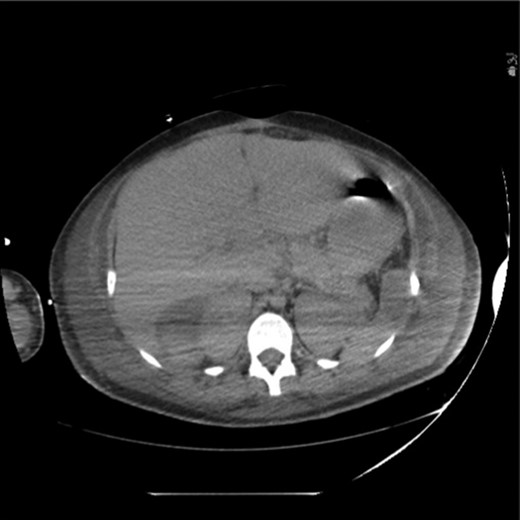

After a post-operative ileus, enteral feeds were restarted on PBD 15 (post-bowel resection Day 11). A CT on PBD 19 for infectious work-up demonstrated resolution of pneumatosis and HPVG (Fig. 6). Excision of the burn wounds began on PBD 4 and was complete on PBD 50. The patient was discharged 2 months after burn injury. At the time of discharge, she had a functioning ileostomy and was tolerating an oral diet with appropriate nutritional parameters. She continues to recover well after her burn surgeries.

CT scan obtained on post-burn Day 19 demonstrating resolution of pneumatosis and hepatic portal venous gas.